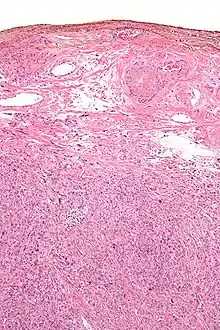

Micrograph showing a silver nitrate (brown) marked surgical margin.

Silver salts have antiseptic properties. In 1881 Credé introduced the use of dilute solutions of AgNO3 in newborn babies' eyes at birth to prevent contraction of gonorrhea from the mother, which could cause blindness. (Modern antibiotics are now used instead).[15][16][17]